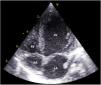

We report the case of a four-month-old infant with Down's syndrome referred for observation due to progressive tachypnea and failure to thrive. Chest radiography revealed cardiomegaly and pulmonary congestion (Figure 1). Transthoracic echocardiography showed severely dilated left-sided chambers with global systolic dysfunction, but was inconclusive regarding the underlying abnormality due to the patient's poor acoustic window (Figure 2). On cardiac catheterization, the child was found to have a 10 mm long, 3.8 mm wide patent ductus arteriosus, anatomically unsuitable for percutaneous closure, and a hypoplastic left coronary artery (Figure 3). The patient underwent an uneventful surgical ligation of the ductus via lateral thoracotomy and was discharged after six days. One month later, the child was admitted to the pediatric ICU with respiratory failure requiring mechanical ventilation. Transthoracic echocardiography revealed a severely dilated left ventricle with dyskinesia of the posterior and lateral walls. Due to lack of clinical improvement, a cardiac computed tomography was performed, revealing a large type I aortopulmonary window (10 mm×10 mm) between the right aspect of the distal pulmonary trunk and the left aspect of the ascending aorta (Figure 4). After surgical closure with an aortic cuff, the patient presented gradual clinical recovery until discharge with residual systolic dysfunction and tachypnea. Through careful analysis, the aortopulmonary window was found to be already visible on the catheterization cines, but was probably overlooked due to the concomitant ductus. The authors wish to highlight that, even in the presence of a common congenital heart defect, additional abnormalities must always be carefully excluded.